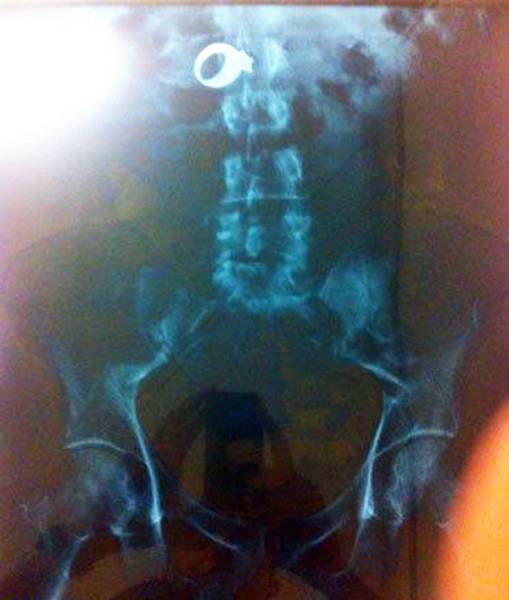

A wedding ring.